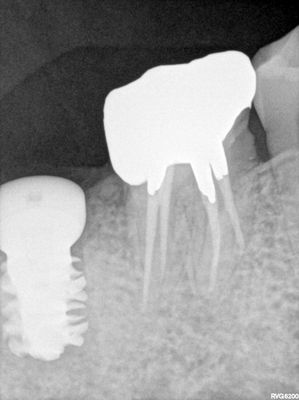

ALai - 47 guided surgery

difficult to get access due to limited interarch space in this region of the mouth. Was able to get 7mm in with first drill, well positioned. Some softer bone where the previous socket was, first implant placed had poor stabiltiy, replaced with wider one, good stabiltiy, placed some bone around buccal distal defect prior to suturing.